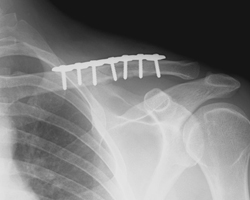

Operative Fixation of Clavicle Fractures

The clavicle (collarbone) fracture is one of the most commonly seen broken bones, fracture of the humeral head (the ball) is quite common an older person who falls.